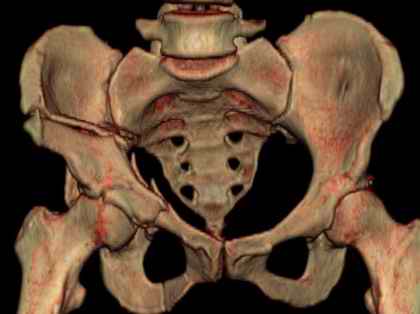

Посылаю схемы и 3D реконструкцию подобного повреждения. Называется он полным высоким двухколонным переломом вертлужной впадины, а "переломы крыла и тела подвздошной кости" входят в это понятие.

прикладываю схему доступа и случай.